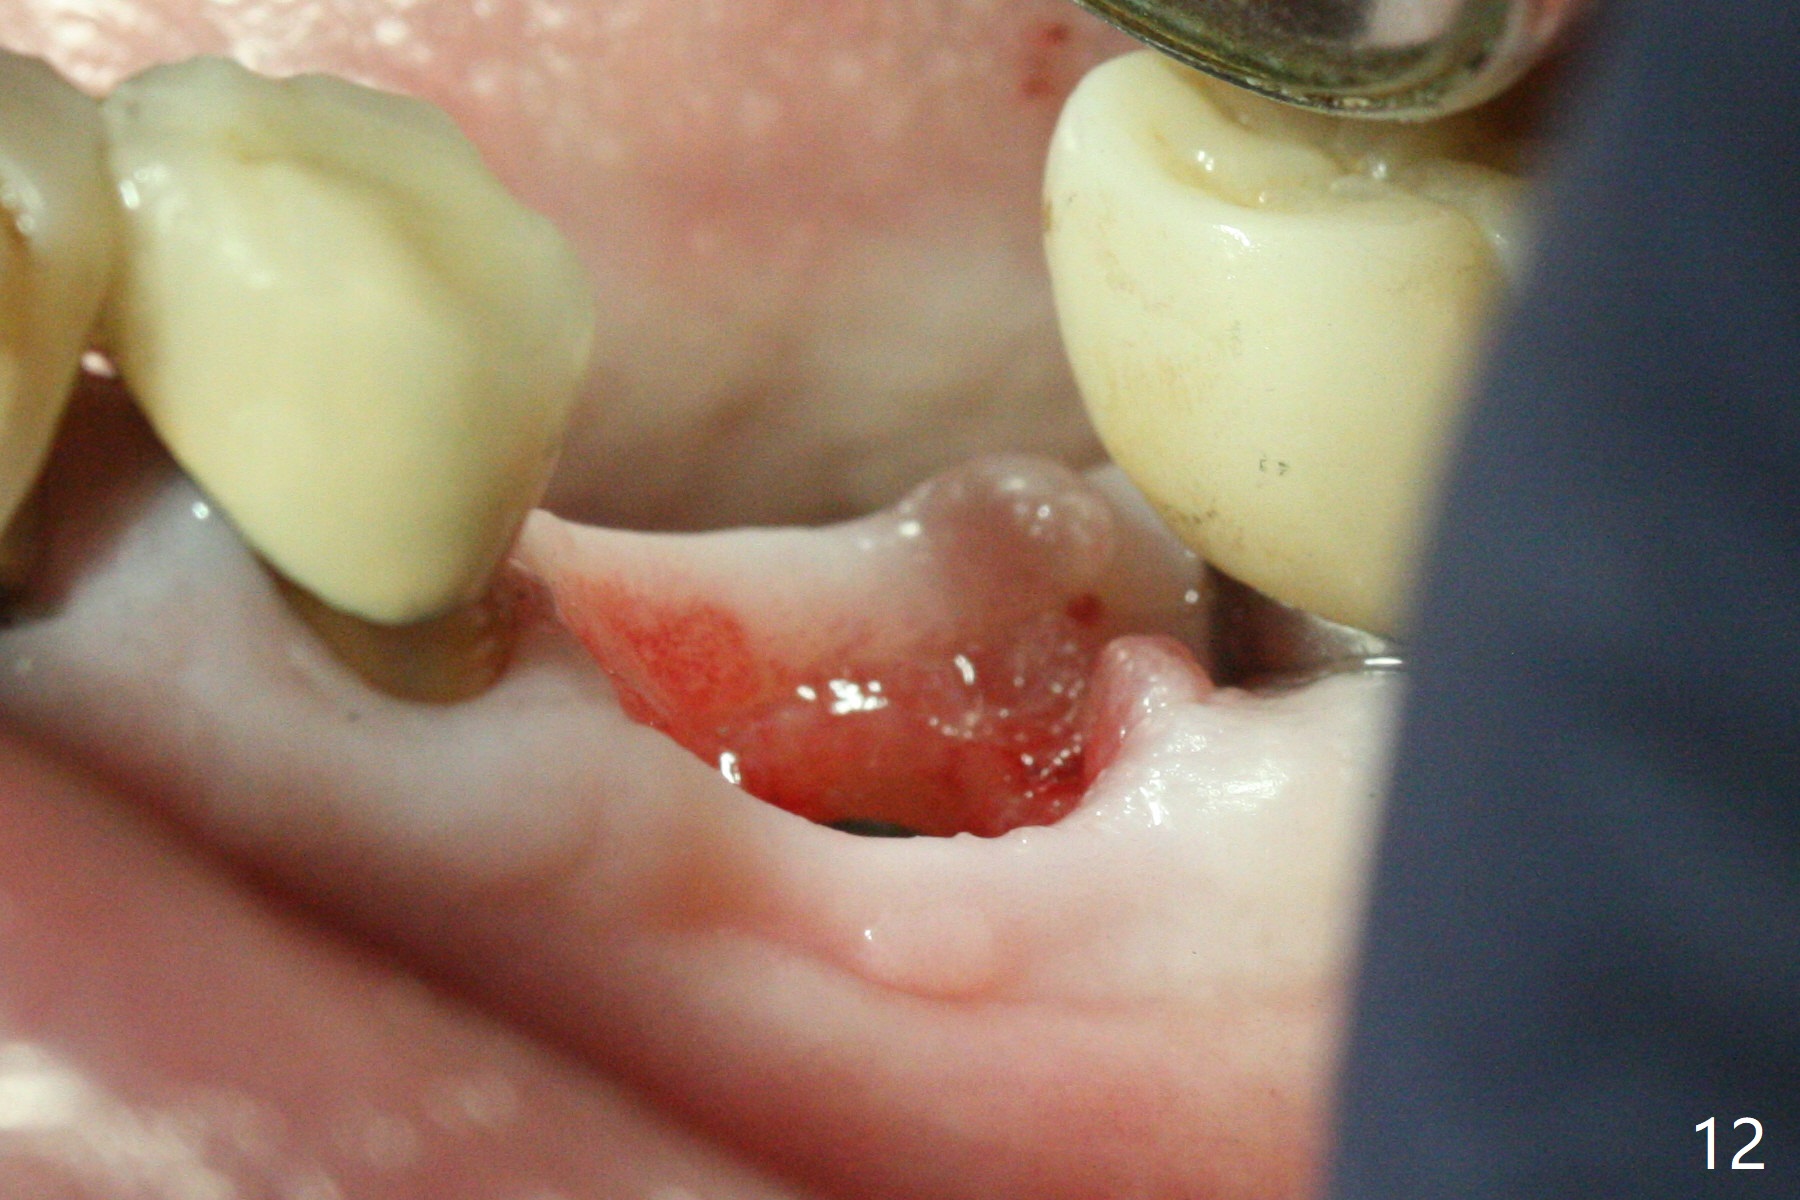

Extraction of the residual roots at #19 (Fig.1) is difficult, partially due to the hard one. The latter contributes to primary stability of 5x10 mm IS implant placed in the septum (Fig.2 (*),3). After change of cementation abutment (5.2x4.5(2) mm (short for provisional)) to hexed temporary abutment (5.2x8(2) mm), Collagen plug and Vera Graft are placed in the remaining mesial and distal socket (Fig.4 *). The last PA is taken when the temporary abutment (Fig.6 (<: hexed portion)) and provisional (P) are removed for modification. Before the abutment/provisional complex returns, a 2nd round of graft is placed (Fig.5 *). After the complex is seated, a 3rd round of graft is placed buccally (Fig.7). The temporary abutment is retightened 2 months postop (Fig.8). The implant appears to be osteointegrated 3.5 months postop (Fig.9). The gingiva looks healthy with (Fig.10) and without the provisional (Fig.11,12). It appears that there is no or minimal buccal plate loss. After insertion of a 5.7 x3 mm 15 degree (B-type) angled abutment (Fig.13) and height adjustment, impression is taken. The provisional is reseated after impression. The mesial bony defect seems to have been repaired nearly 8 months postop, 3 months post cementation (Fig.14 *). The bone density increases mesially 11 months post cementation (Fig.15).